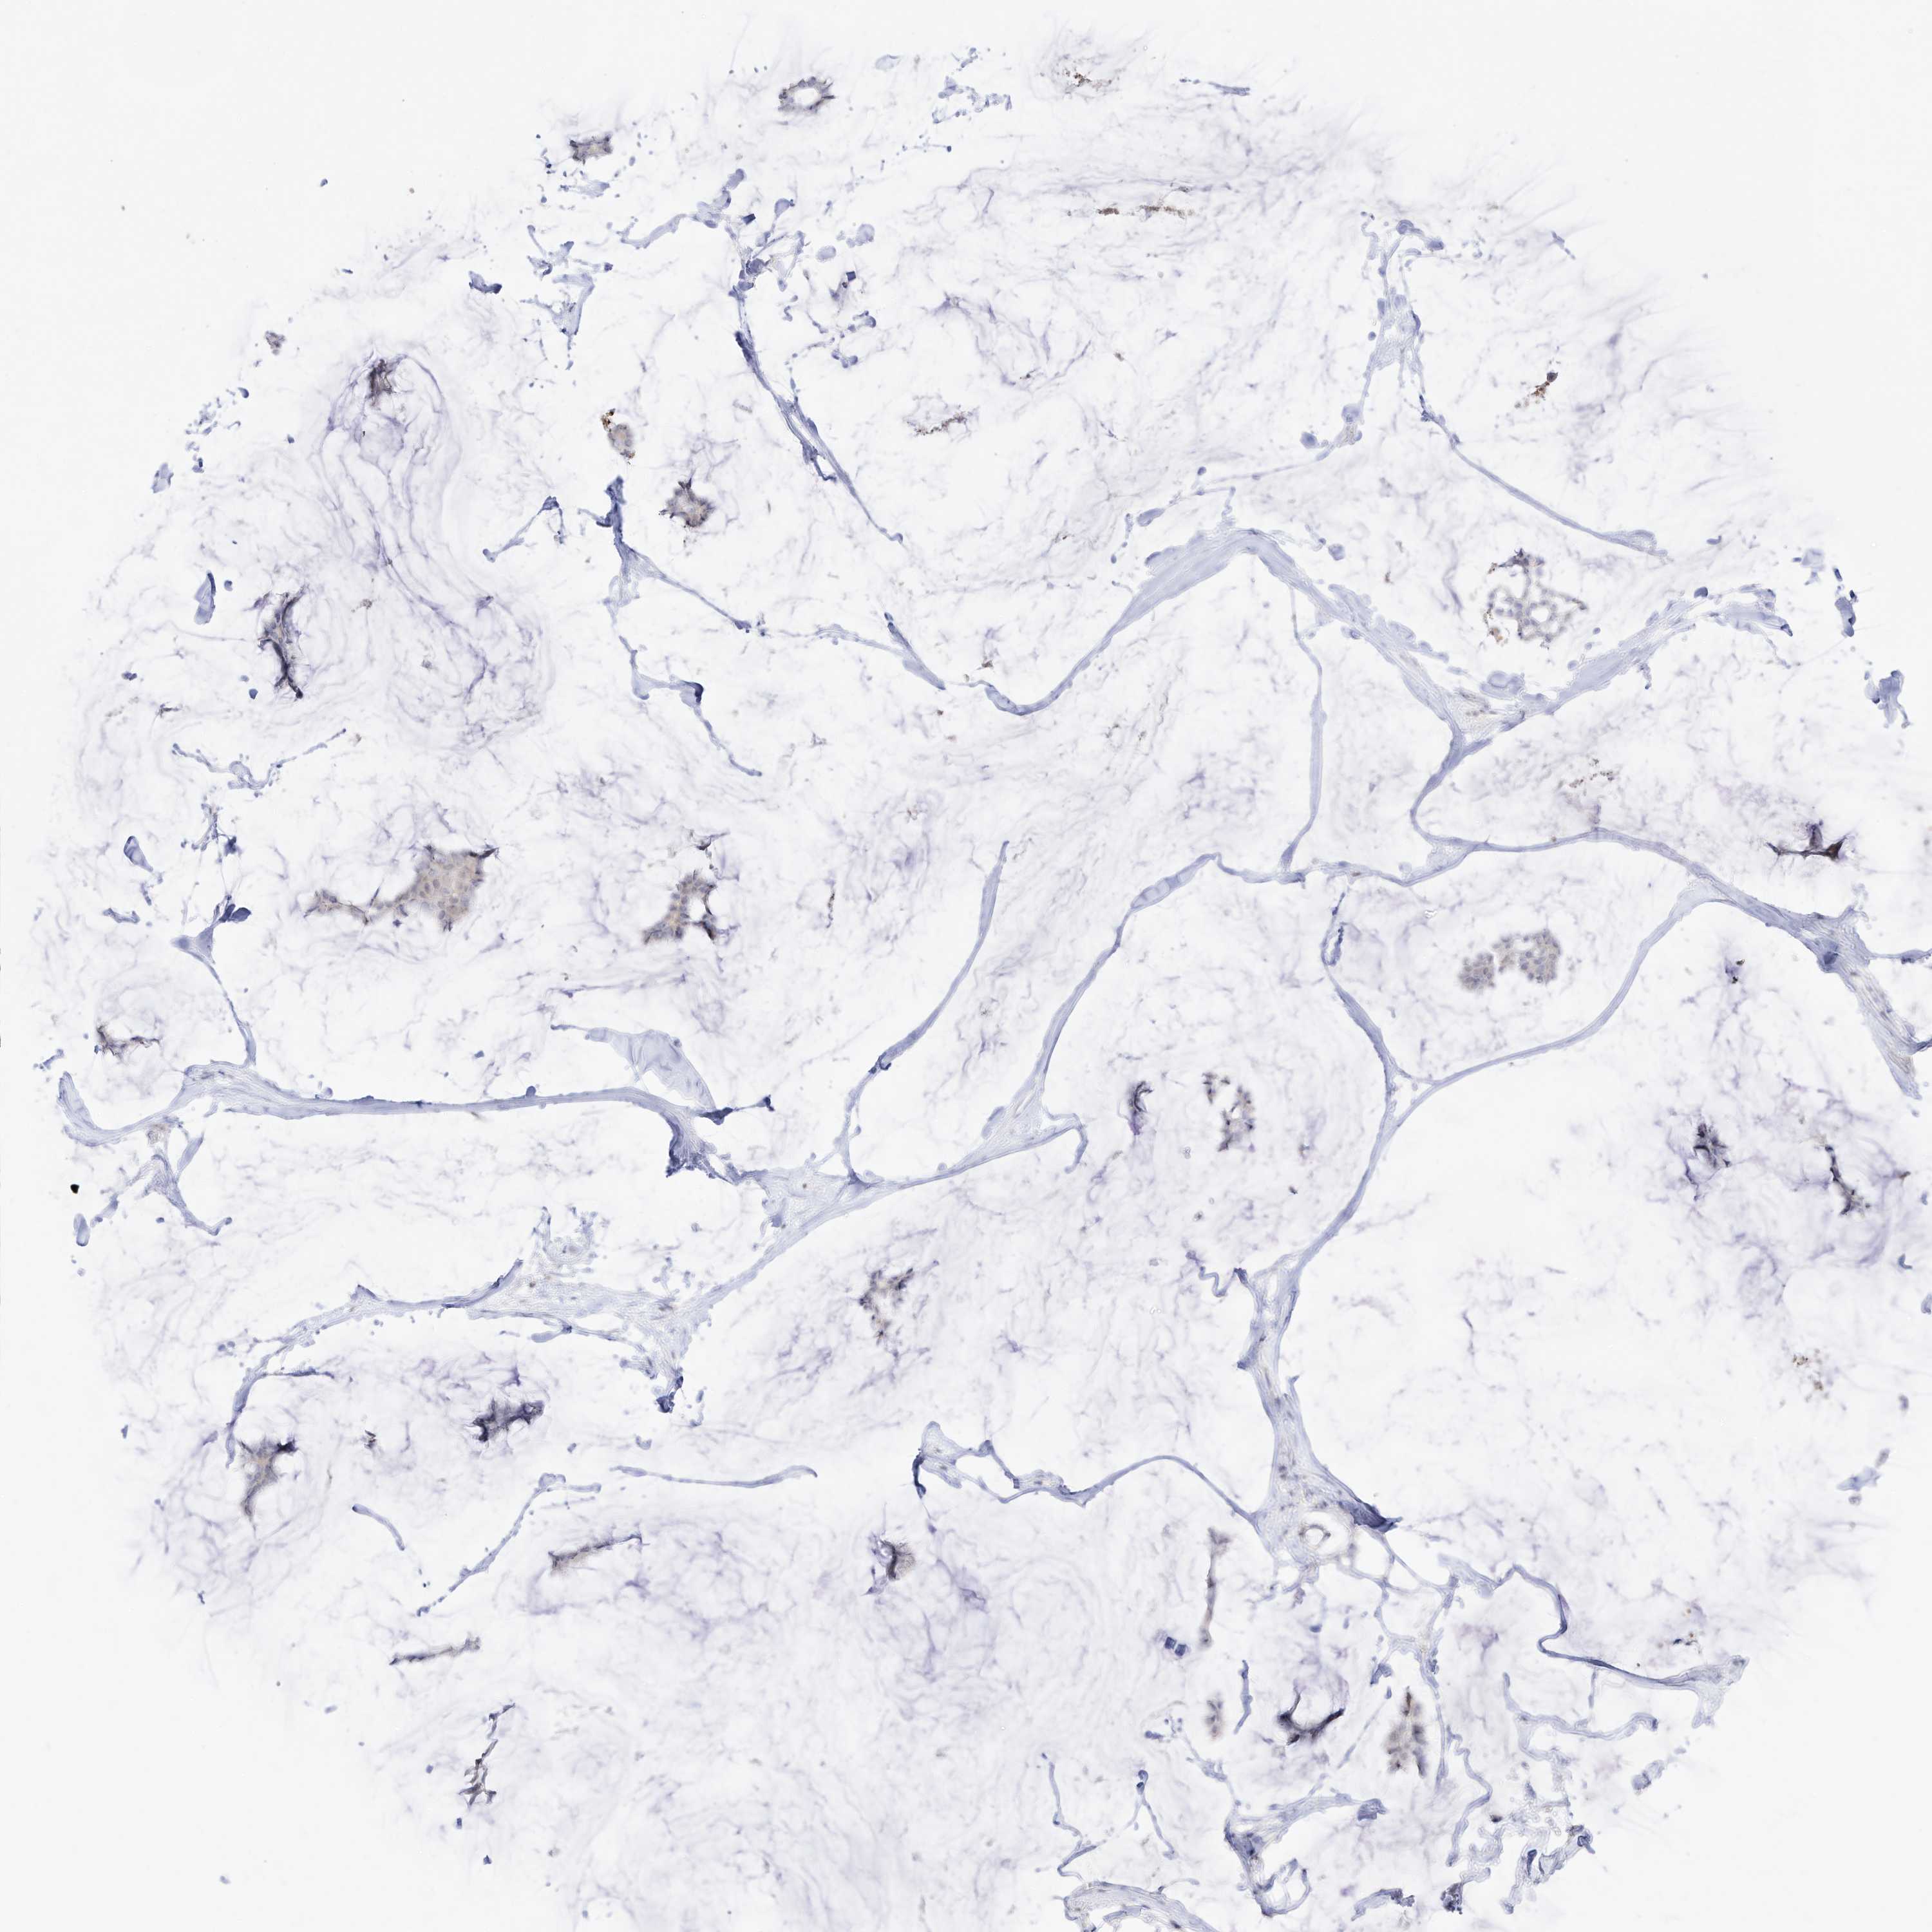

BRCA TCGA BRCA VALIDATION PROTEIN EXPRESSION

ANTIBODIES

AND

VALIDATION